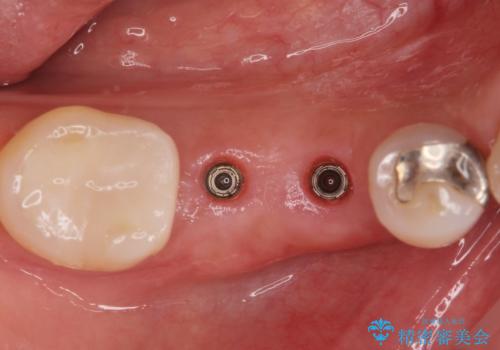

無事インプラントが入りました。

インプラント治療をしてもメンテナンスを怠っているとインプラント歯周炎になるリスクがあがるのでメンテナンスをお勧めします。